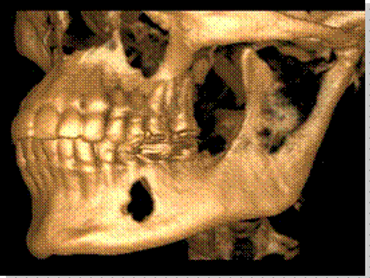

What is CBCT- Cone Beam Computer Tomography?

CBCT is a digital x-ray scanner specifically designed for scanning the head and jaws. The scanner rotates 360 degrees around the patient's head in a matter of seconds. The x-ray is a low energy fixed anode tube similarly used in panoramic machines. This method reduces radiation scatter common to most conventional x-rays. The cone shaped x-ray provides 360 views that can be presented in 2D image and 3D volume for advanced planning and diagnostic support.

[Why the need for a CBCT?]

This one scan provides more images than plain film conventional imaging, with complete visualization of the patient's entire maxillofacial region. These images clearly display TM disorders, impacted teeth, critical bone and tooth relationships, oral- nasal airways, para-nasal sinus, mandibular canal and difficult to see pathologies within one volume. The user friendly software system reconstructs true size, distortion free, high resolution images.

[Why is this better for patients?]

The CBCT scanner is fast, comfortable (nothing goes in the mouth), and painless for patients. It provides a complete set of maxillofacial images with less radiation than conventional orthodontic and medical type CT work-ups. CBCT now can re-create true size cephalometric and panoramic images, virtually eliminating the need for conventional orthodontic x-rays, so your patients will be comforted by the knowledge that you have all the information needed to evaluate and plan their treatment